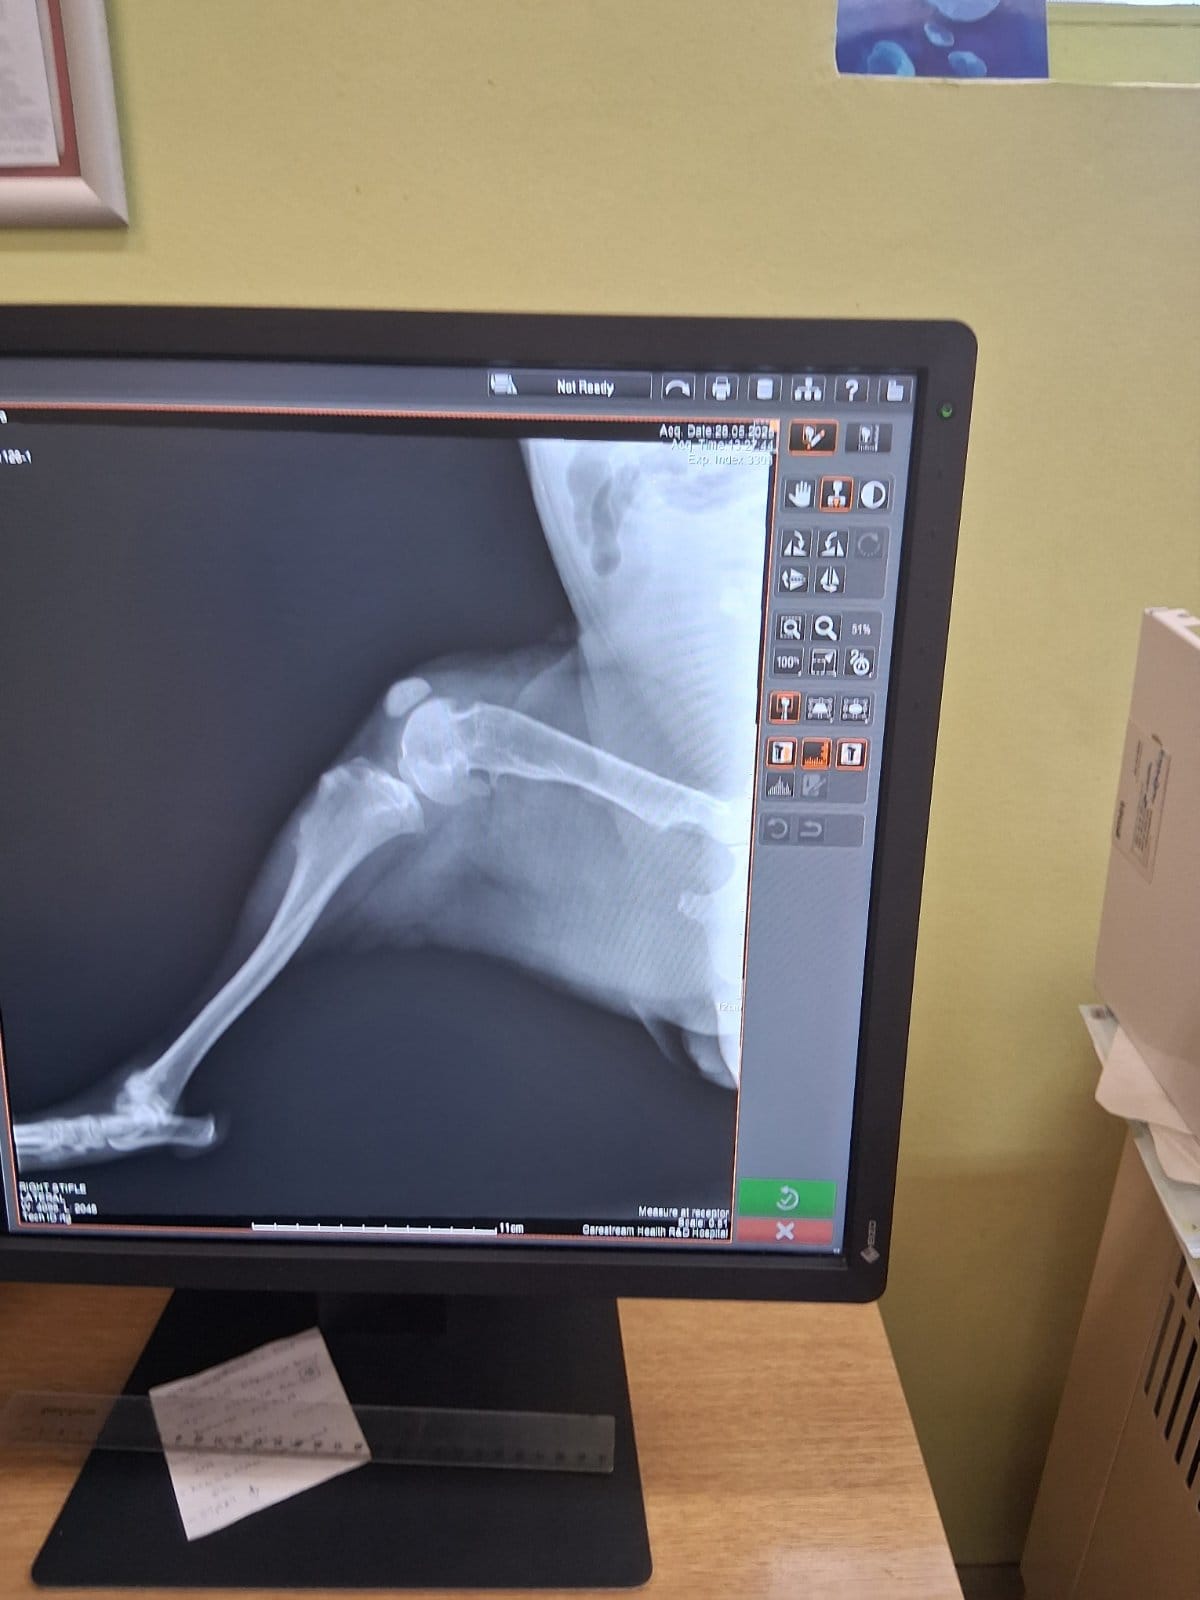

Im September 2025 haben wir Ihnen die kleine Finija vorgestellt: Gerade einmal vier Monate alt, wurde sie in einem erschütternden Zustand gefunden. Beide Hinterbeine waren gebrochen, eine Fortbewegung war für sie nur noch auf den Vorderpfoten möglich. Trotz starker Schmerzen zeigte Finija eine unglaubliche Willenskraft – ein kurzes Video aus…